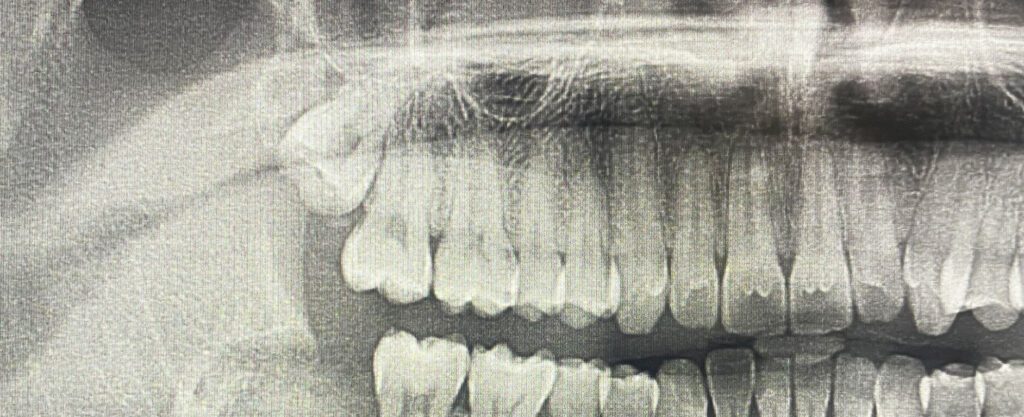

Przede wszystkim oczywiście należy udać się do dentysty! Na podstawie przeglądu i zdjęcia RTG stomatolog oceni charakter problemu i dobierze właściwą metodę postępowania. Najczęściej jest to chirurgiczne usunięcie zatrzymanego zęba: chirurg dokonuje nacięcia dziąsła, żeby uzyskać dostęp do zatrzymanego zęba. W przypadku zatrzymania częściowego, specjalista rozcina błonę śluzową nad zębem, natomiast przy zębie całkowicie zatrzymanym w kości uzyskuje dostęp do niego wycinając niedużą część kości nad zębem. Rozpreparowanie korzeni jest następnym krokiem, po nim zaś dochodzi do dłutowania (rozchwiania korzeni za pomocą dźwigni). W ostatnim kroku wyjmuje korzenie za pomocą kleszczy chirurgicznych.